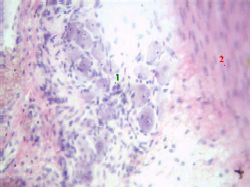

| Отличия: 2) вид эпителия | Второй признак - эпителий, егоповерхностные слои: в мочевом пузыре ядра поверхностных клеток опять-таки являются круглыми (переходный эпителий), на нижней поверхностиязыка ядра поверхностных клеток – плоские (многослойный плоский неороговевающий эпителий), | б) Мочевой пузырь. Большое увеличение Полный размер |

а на верхней поверхности языка нитевидные сосочки обычно заканчиваются длинным роговым стержнем (многослойный плоский, частично ороговевающий эпителий). |

| Интра- муральный ганглий | а) А на данном снимке между слоями мышечной оболочки (2) мочевого пузыря виден интрамуральный ганглий (1). б) В его составе - крупные тела нейроцитов, окружённые глиальными и соединительнотканными клетками. | Полный размер |